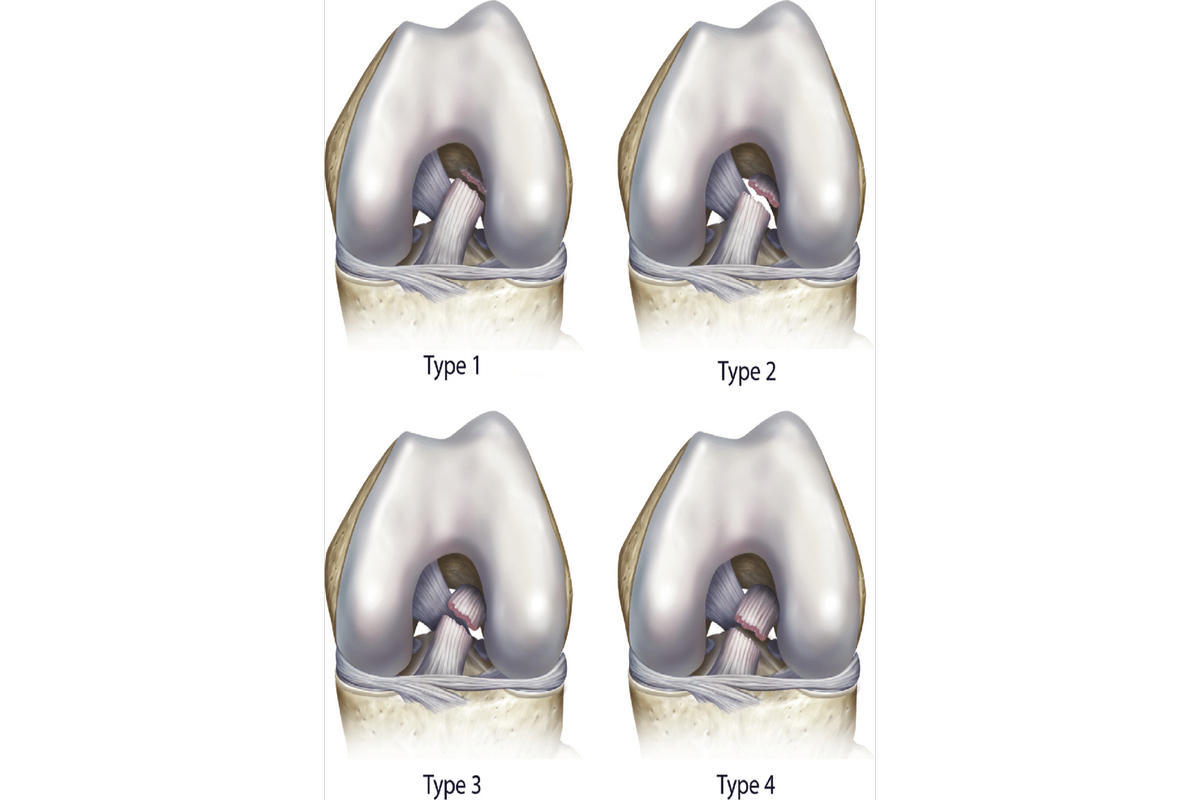

Ακτινογραφίες για αποκλεισμό οστικών κακώσεων

Μαγνητική τομογραφία (MRI), που επιβεβαιώνει τη ρήξη πρόσθιου χιαστού και αναδεικνύει συνοδές βλάβες σε μηνίσκους, χόνδρο ή πλάγιους συνδέσμους

Η MRI αποτελεί την εξέταση εκλογής για την τεκμηρίωση της βλάβης.